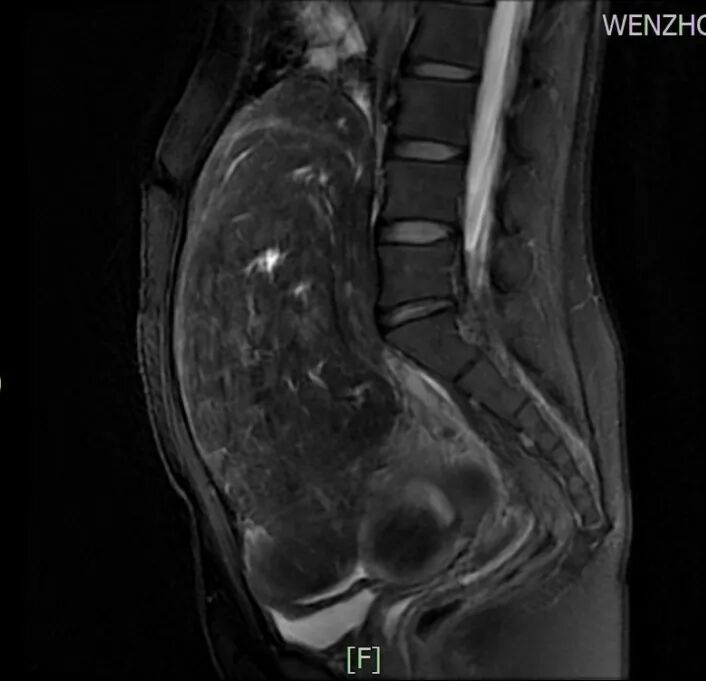

所幸经过B超检查提示“子宫多发肌瘤,肌层内见多个低回声团块,最大者位于宫底部,大小约203x103x184mm,边界清,突向浆膜外,内部回声不均匀”,磁共振检查也支持B超诊断。面对忧心忡忡的刘女士,陈主任苦口婆心,经过仔细询问病史结合辅助检查结果等,为她制定了“经脐单孔免气腹腹腔镜下子宫肌瘤剥除术”的手术方案。

1-2刘女士磁共振图片